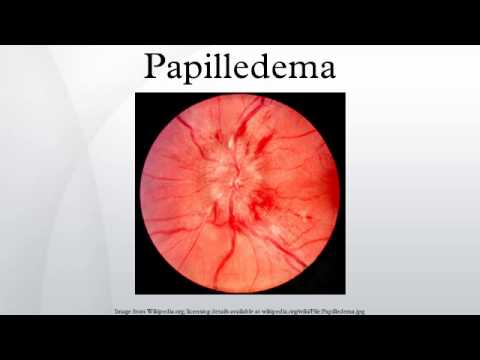

late sign of increased intracranial pressure